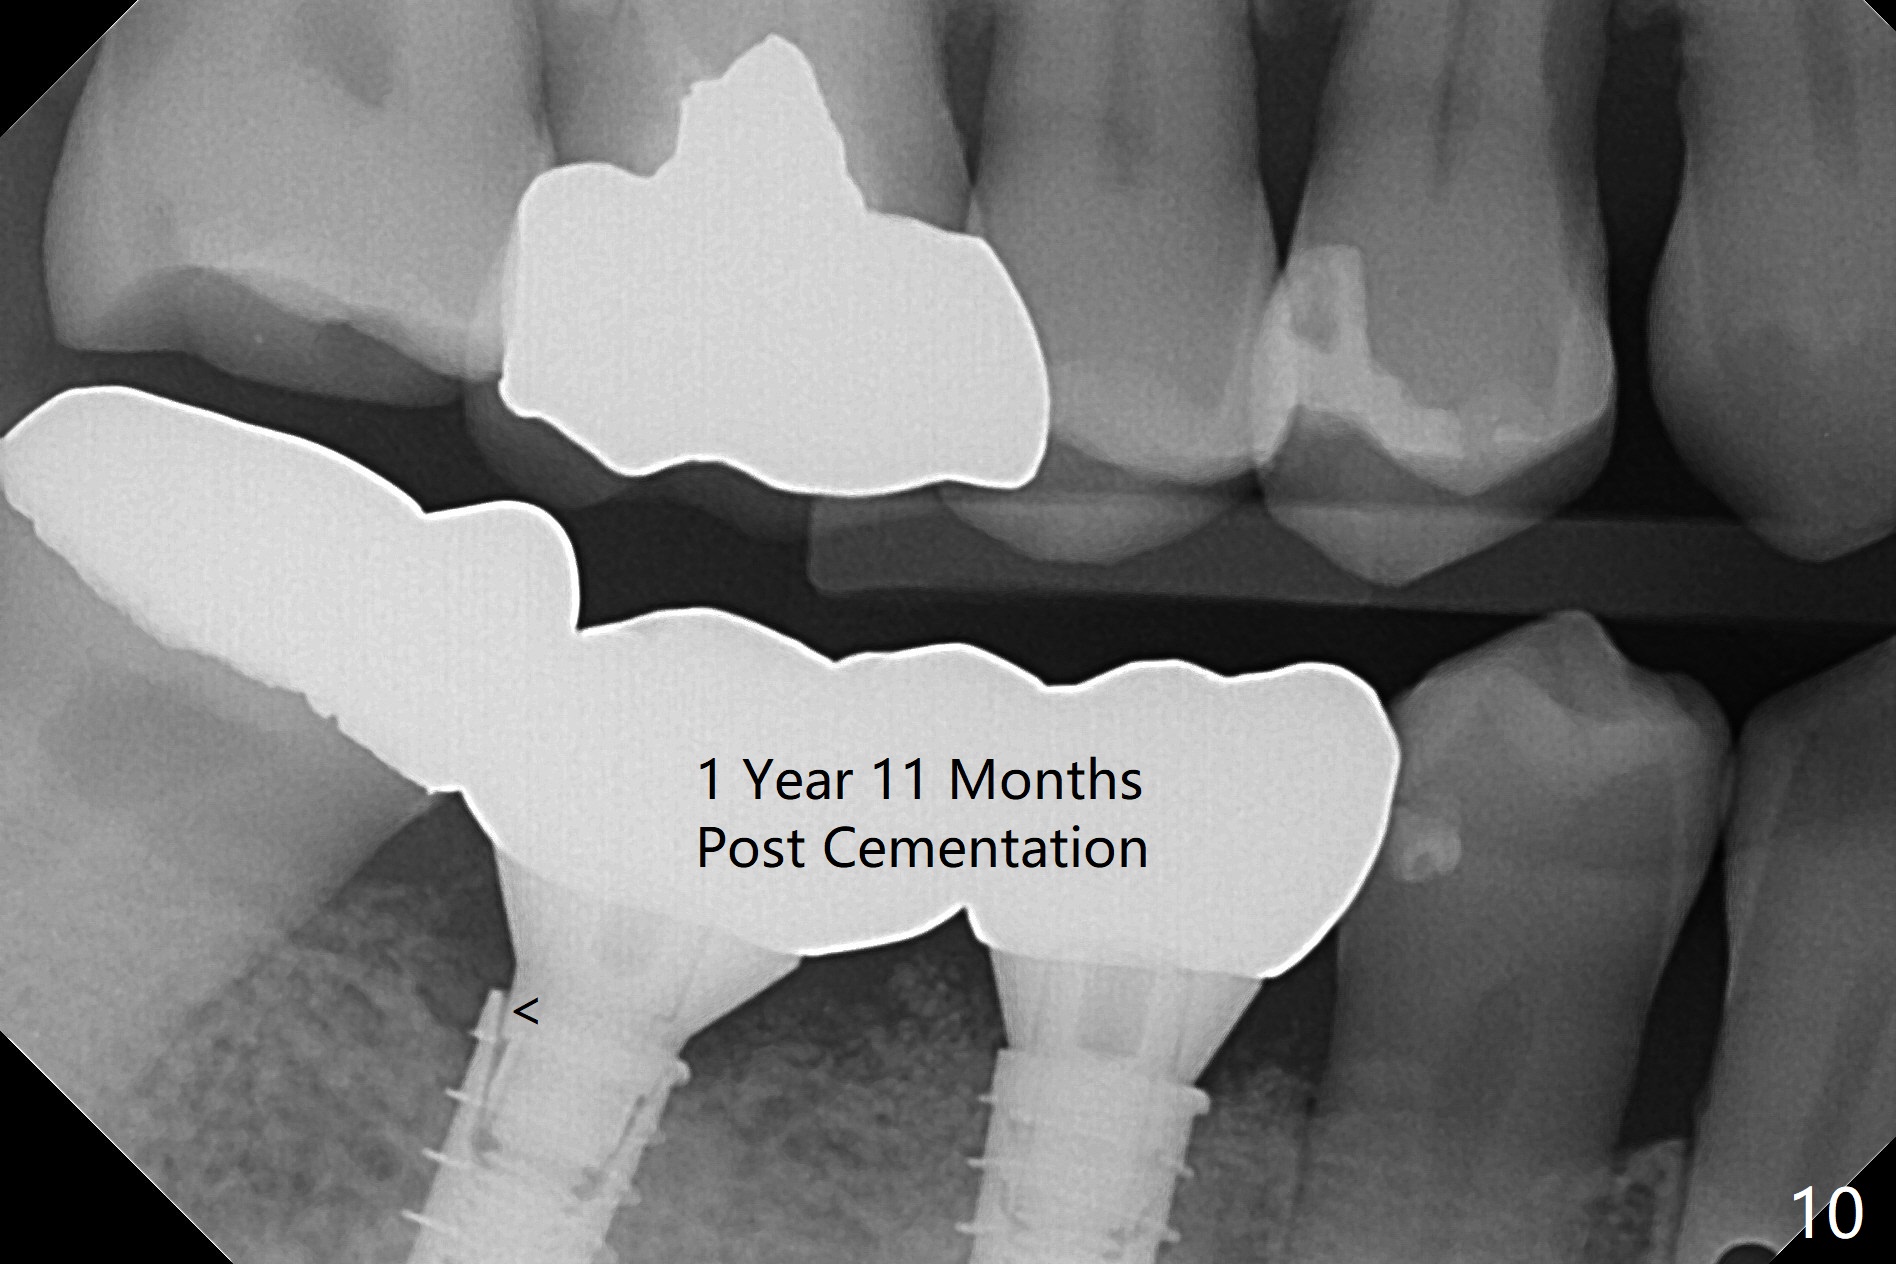

After incision, the ridge at #29 and 30 is found ~ 5 mm wide buccolingually. To place a 4x11 mm IBS implant at #30, the ridge is expanded using BEB technique (bone expansion and bending, Fig.1). It appears that the initial osteotomy at #29 is mesial (Fig.1 yellow dashed line: the distal surface of the root of the tooth #28). After moving the osteotomy distal, the final implant position at #29 (4x11 mm) is within normal limit (Fig.2). The bone at #29 seems to be not so dense that bending (using 1.6 mm drill) is not necessary (using Magic Split and Magic Expanders 3 and 3.8 mm). Later the implant at #30 (4x11 mm) is placed deeper (Fig.3). After placing bone graft around the implants/abutments and suturing, the ridge looks wider with apparent formation of the gingival bands around the abutments (Fig.4 *). Three months and a half postop, bone loss is minimal (Fig.5) and gingival bands forms around the abutments (Fig.6). Fig.7 is taken 1 month post cementation (panoramic X-ray). The patient chews normally 1 year (Fig.8) and nearly 2 years (Fig.9,10) post cementation. The crown at #31 needs recementation 2 years 7 months post #30 cementation; the incomplete seating of the abutment was noted for the first time (Fig.11). Five months later the patient is going to be retired and wants to travel abroad. After approval, the access hole was reopened; articulating paper shows under occlusion of the crown (Fig.12). Since the gap between the abutment and the implant is large, the abutment/crown complex seems to be necessary to be turned (Fig.13 curved arrow). The proximal surfaces of the crown need to be trimmed (straight lines). After turning, the crown sits down with screw tightening; the patient feels pain from the gingival cuff (Fig.14). After turning, the abutment appears to be completely seated (Fig.15). In fact the mesial and distal surfaces of the crown should have clearance from the neighboring teeth (Fig.14) so that pick-up impression is able to hold the crown/abutment complex securely (Fig.16: *). The crown is separated from the abutment after crown repair. They are seated together (loose connection) using the crown as a guide to seat the abutment. BW is taken without the crown. It appears that the abutment remains seated completely (Fig.17). The apical space is equal between #29 and 30 (Fig.17, as compared to Fig.5).